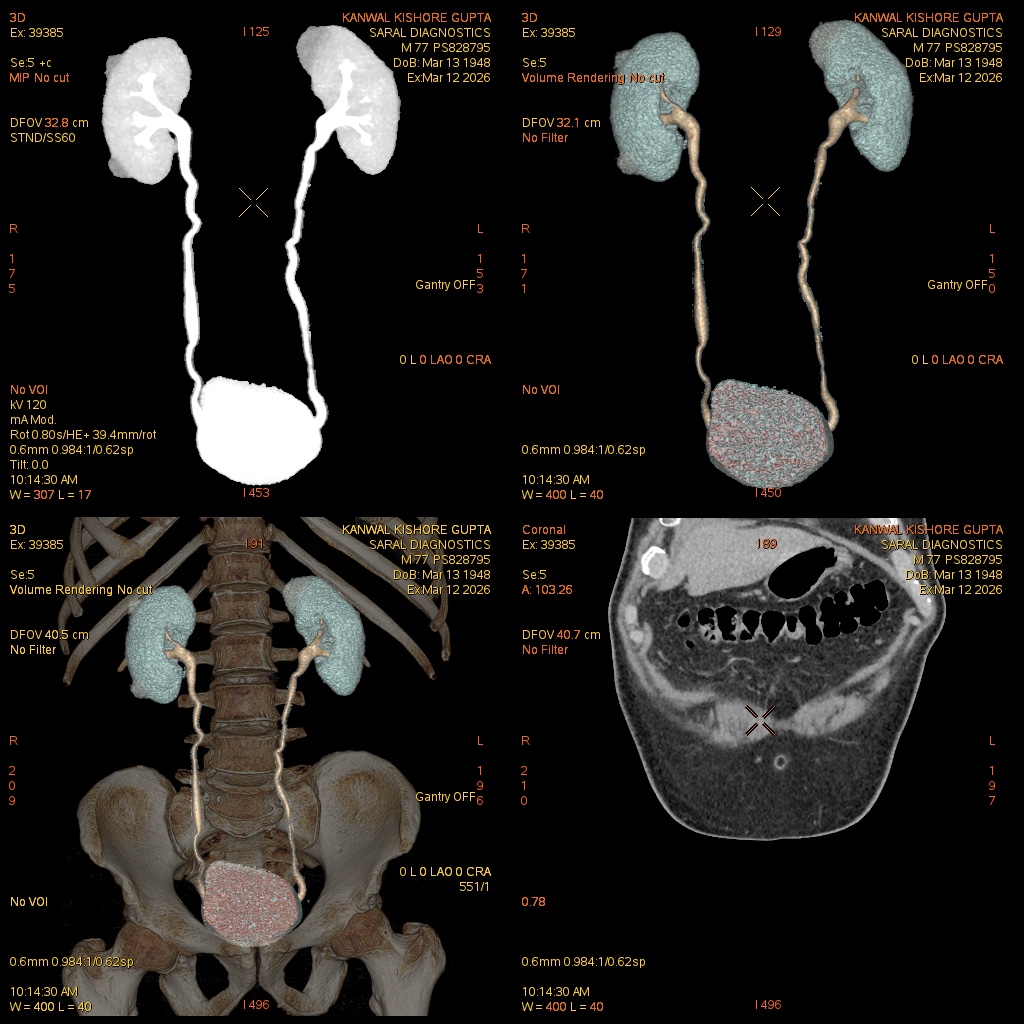

Reference Image

Urography (Scan Chages Only)